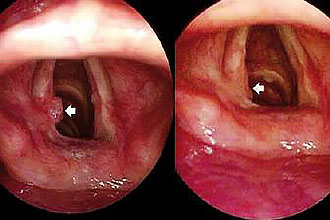

Не леченный патологический процесс осложняется острым стенозом гортани. Из диагностических методик назначается мазок из зева и ларингоскопия:

- при остром течении визуализируется гиперемия слизистой гортани, связок, отмечается слизь, однако при гриппе возможны кровоизлияния в слизистую;

- при хроническом – наблюдается застойный отек, гиперемия, некоторое утолщение слизистой, а в просвете гортани визуализируется густая слизь.